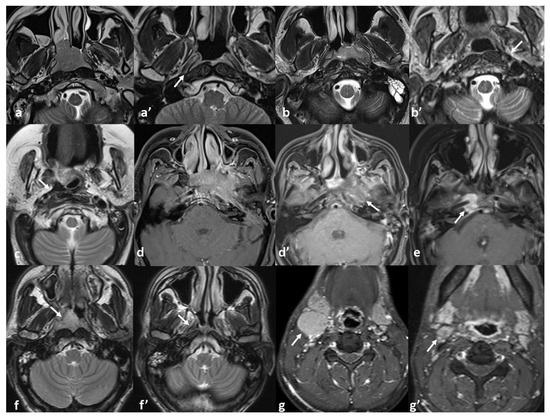

| MRI Response Patterns | Local Tumor Stage | Total | No Recurrence | Recurrence | Total | |||

|---|---|---|---|---|---|---|---|---|

| T1 | T2 | T3 | T4 | |||||

| Complete resolution without any sequel signal abnormality | 72% (n = 5) | 29% (n = 7) | 0% (n = 0) | 0% (n = 0) | 23% (n = 12) | 92% (n = 11) | 8% (n = 1) | n = 12 |

| Thin fibrosis at the primary tumor site | 14% (n = 1) | 21% (n = 5) | 36% (n = 4) | 0% (n = 0) | 19% (n = 10) | 90% (n = 9) | 10% (n = 1) | n = 10 |

| Bulky fibrosis without discernible soft tissue or enhancement | 0% (n = 0) | 21% (n = 5) | 46% (n = 5) | 10% (n = 1) | 21% (n = 11) | 73% (n = 8) | 27% (n = 3) | n = 11 |

| Heterogeneous signal with subtle contrast enhancement | 0% (n = 0) | 12% (n = 3) | 18% (n = 2) | 30% (n = 3) | 15% (n = 8) | 50% (n = 4) | 50% (n = 4) | n = 8 |

| Residual enhancing soft tissue | 0% (n = 0) | 0% (n = 0) | 0% (n = 0) | 60% (n = 6) | 12% (n = 6) | 17% (n = 1) | 83% (n = 5) | n = 6 |

| Complete resolution at the primary site with persistent nodal disease | 14% (n = 1) | 17% (n = 4) | 0% (n = 0) | 0% (n = 0) | 10% (n = 5) | 100% (n = 5) | 0% (n = 0) | n = 5 |

| Total | 100% (n = 7) | 100% (n = 24) | 100% (n = 11) | 100% (n = 10) | 100% (n = 52) | 73% (n = 38) | 27% (n = 14) | 100% (n = 52) |

| p < 0.001 * (tau-b = 0.43) | p = 0.004 * (χ2) | |||||||